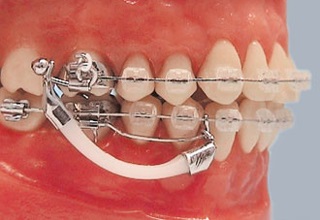

Fotografii cu exemple de dispozitive ortodontice

Alegerea unui dispozitiv ortodontic depinde de complexitatea corecției efectuate, de dorințele clientului clinicii, precum și de alte criterii, cum ar fi costul și durata tratamentului.

O fotografie cu exemple de utilizare a dispozitivelor ortodontice înainte și după

Toate dispozitivele pe care ortodontul le utilizează în lucrarea sa sunt detașabile și nu pot fi îndepărtate. Printre acestea se numără și cele pe care se poate purta un anumit număr de ore pe zi. Acestea sunt folosite de copiii cu mușcături mixte și cu lapte. Dispozitivele ortodontice se găsesc:

Ortodontic cu o singură jawă

Primele sunt considerate mai eficiente, costul acestora este ușor diferit de cel din urmă. Puteți citi despre ele pe site-ul nostru.

Aparatul dvuhsheljustnye afectează dezvoltarea și creșterea maxilarului, poate dezactiva de obiceiurile proaste care au un efect negativ asupra formării mușcăturii. La baza lor, acestea sunt protezele dentare obișnuite, având un aspect diferit.